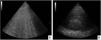

Chest imagesImaging criteria should include bilateral infiltrates on CXR or CT. Additionally, lung ultrasound (evidence of B-lines or consolidation, Fig. 2A and B) is incorporated in this update. Whichever modality is used, it should suggest loss of aeration not fully explained by lobar collapse, pulmonary nodules or pleural effusion.

Therefore, the New Global Definition of ARDS integrates lung ultrasound to detect the loss of aeration, especially when CXR or CT is not available. This technique is especially useful when the operator is trained to detect bilateral consolidations and noncardiogenic pulmonary edema. In the modified definition for resource-limited countries, the lack of operator expertise could lead to overdiagnosis of ARDS, since PEEP is eliminated as a diagnostic criterion.

Although the use of lung ultrasound for this purpose could be questioned, there is evidence that supports it as an appropriate complement for imaging diagnosis of ARDS.32 On the other hand, a very recent multicenter study evaluated pulmonary edema with the LUS (Lung Ultrasound Score) score for diagnosis of ARDS. It was demonstrated, through a model then applied successfully to a validation cohort, that LUS has a very good diagnostic performance and could detect ARDS correctly, comparable to that of expert evaluators. these conclusions, however, require validation in larger numbers of patients.23